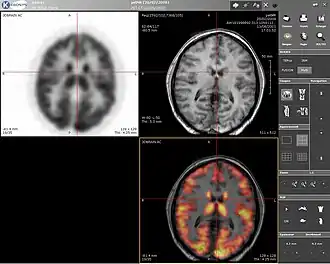

Positron emission tomography (PET) is a nuclear medicine imaging technique which produces a three-dimensional image or picture of functional processes in the body. The theory behind PET is simple enough. First a molecule is tagged with a positron emitting isotope. These positrons annihilate with nearby electrons, emitting two 511 keV photons, directed 180 degrees apart in opposite directions. These photons are then detected by the scanner, which can estimate the density of positron annihilations in a specific area. When enough interactions and annihilations have occurred, the density of the original molecule may be measured in that area. Typical isotopes include 11